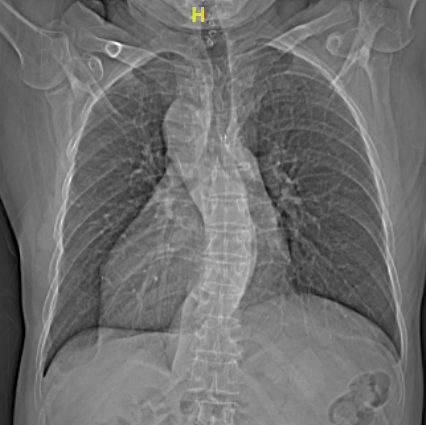

与正常人心脏位置偏左,心尖部在胸腔左侧相反,66岁的梁大叔心脏却长在了右胸腔,好像是正常心脏在镜子里的“影子”,医学上叫做“镜像右位心”。1年前,他一活动就感到心慌气喘,出现反复心悸等症状,被确诊为房颤。

进一步的心脏超声检查发现,梁大叔不仅有右位心,还有永存左上腔的先天性畸形,手术治疗又增加了不少难度。这些先天心脏畸形不仅会造成医生手术操作的不便,而且术中穿刺和导管放置稍有不慎,就可能出现穿孔、大血管损伤、心脏填塞等致命风险。面对如此棘手的手术,不少电生理团队都难以“接招”,梁大叔和家属多方打听,慕名来到吃瓜网 。

不久前引进厦心的亚洲首台心血管专用型CT率先上阵,对患者进行了高精度的心脏扫描,清晰显示了心腔结构、肺静脉及毗邻组织等,为手术开展提供了高质量的影像基础。术中则应用了先进的三维电解剖标测系统,在心腔内超声指导下,常栋、李强两位主任医师率队凭借扎实的手术功底,成功在非常规位置穿刺房间隔,实现了导管精准定位,消融了病灶,更在术中尽可能减少了x线的应用。短短不到三小时,长期困扰梁大叔的房颤终于顺利解除,这颗特殊的心脏也恢复了正常的节奏。